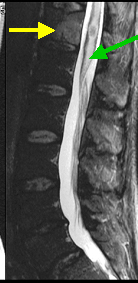

Spinal Cord Compression - Wikipedia, The Free Encyclopedia

Spinal cord compression develops when the spinal cord is compressed by bone fragments from a vertebral fracture, a tumor, (MRI) of the whole spine. [1] The most common causes of cord compression are tumors, but abscesses and granulomas ... Read Article